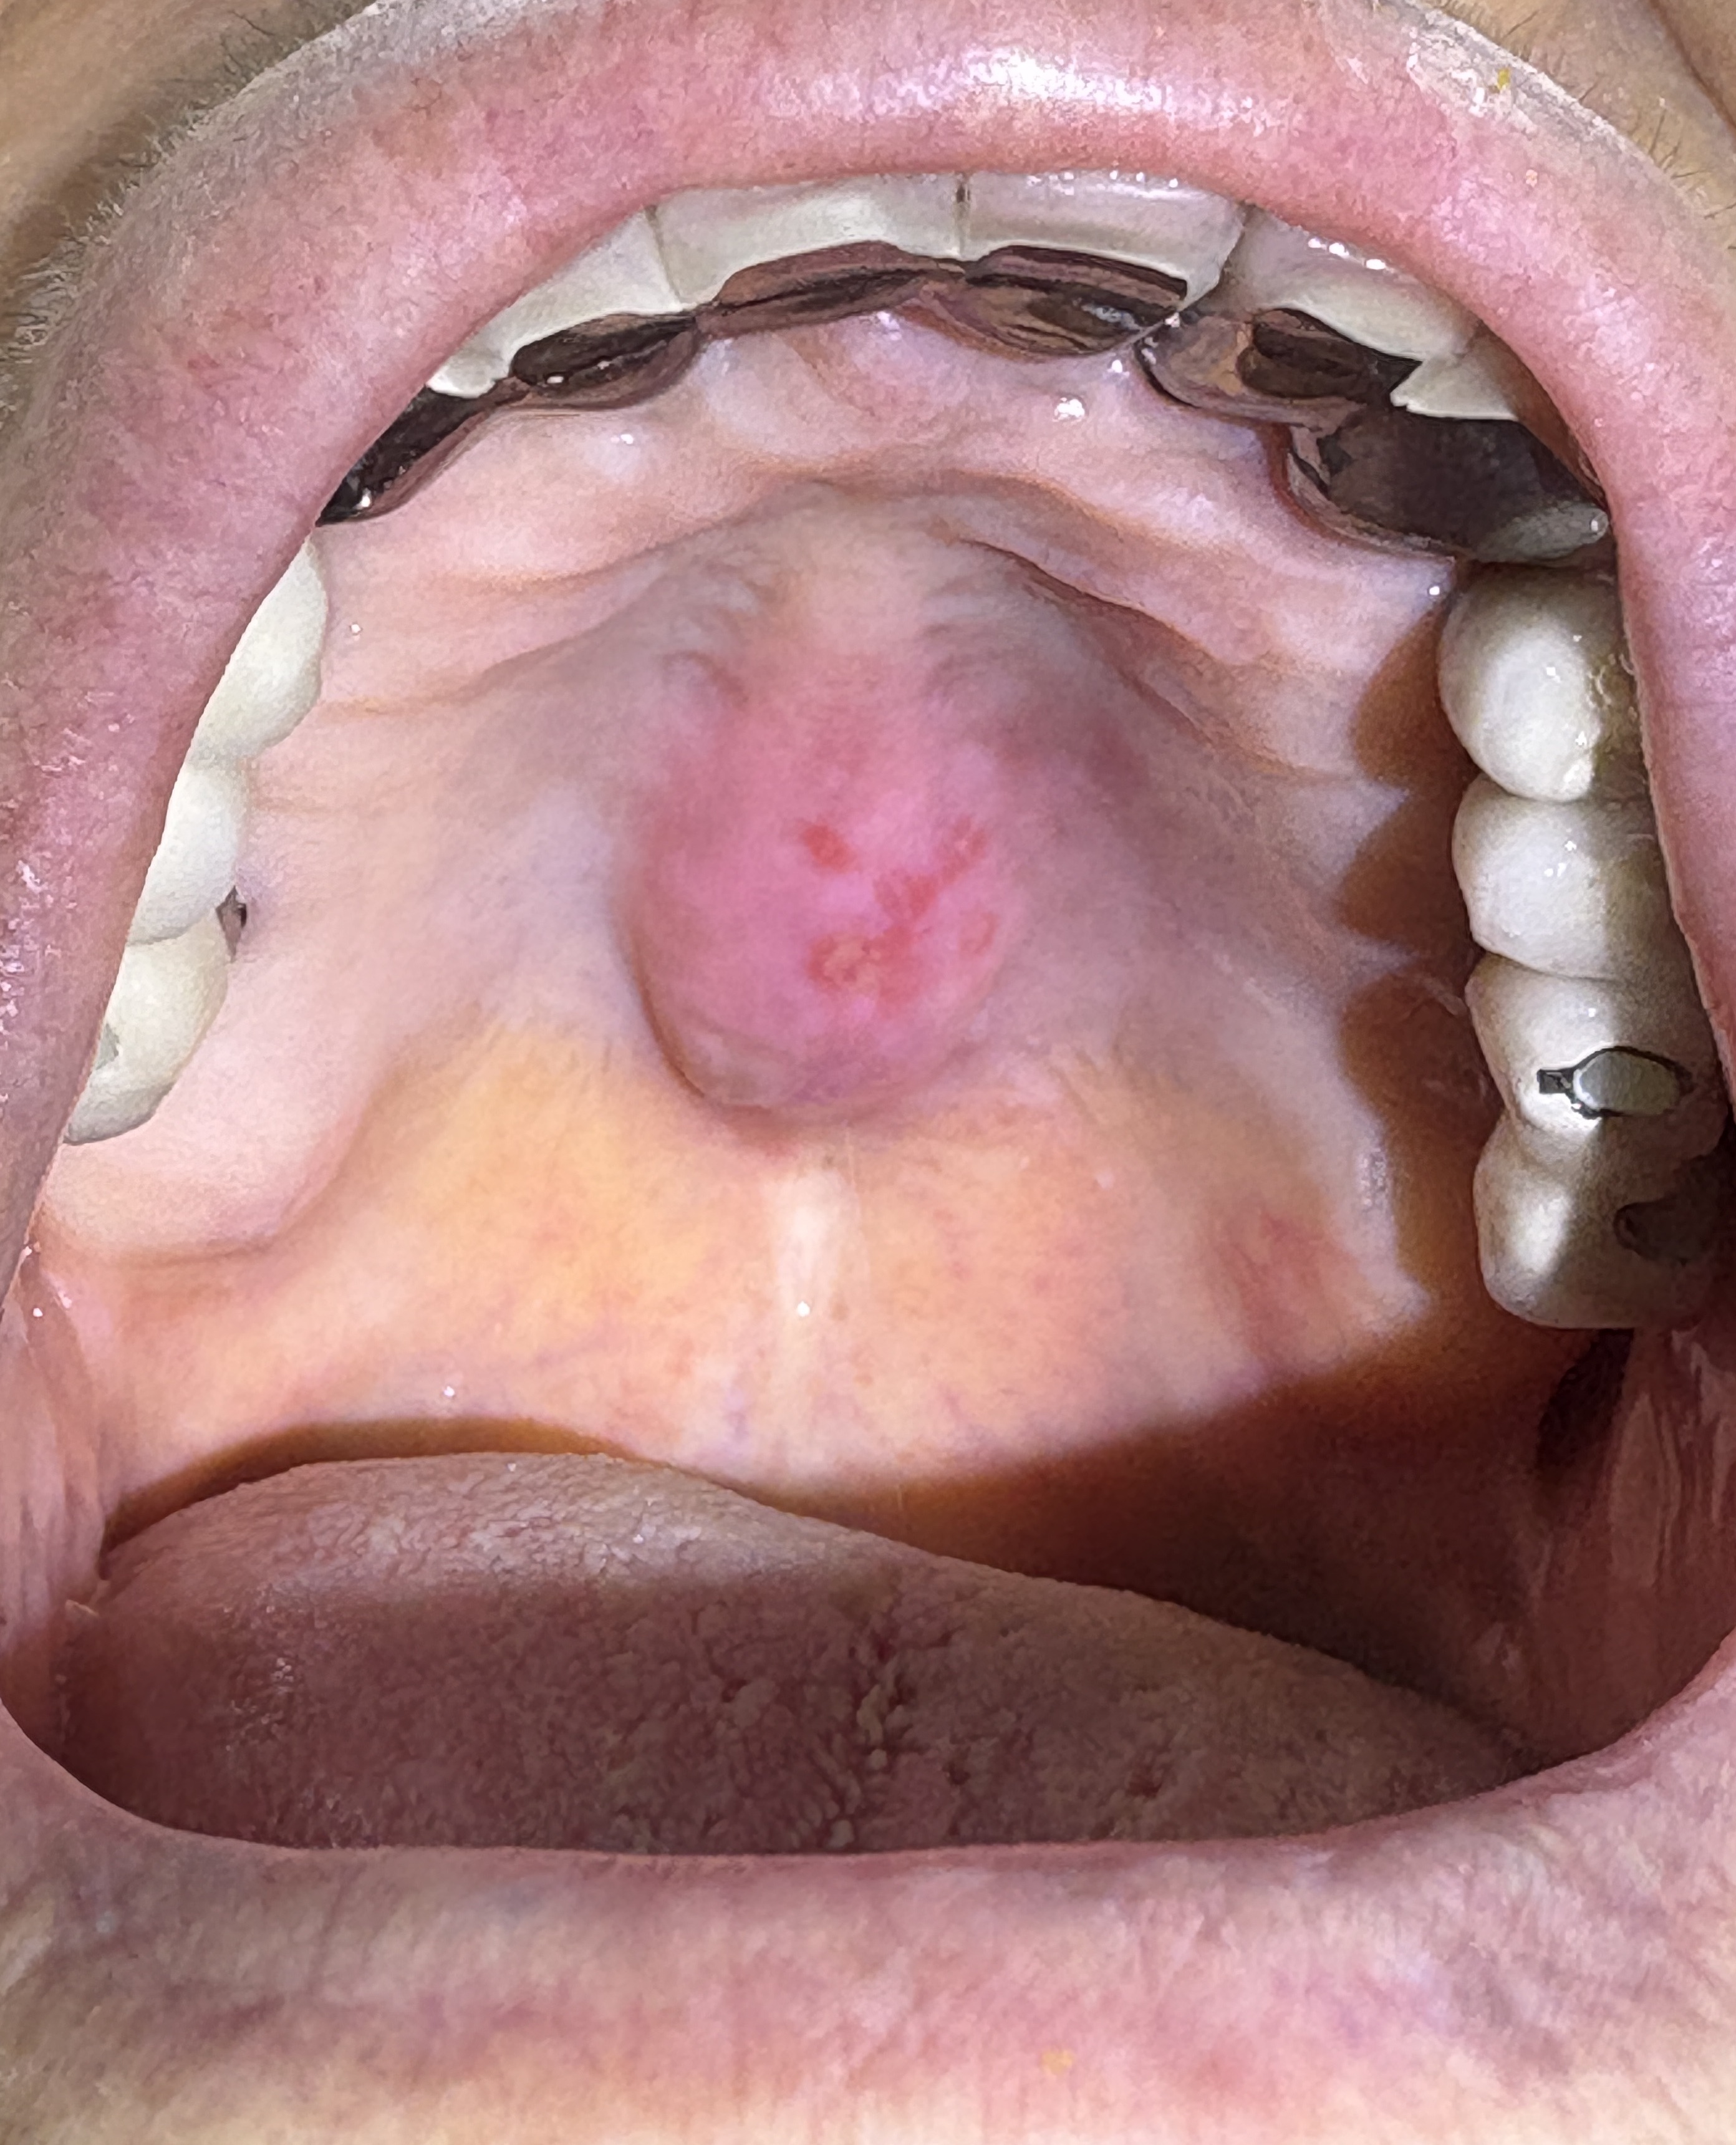

喉を診てみると

上あごの一部が出っ張り、その表面に口内炎が出来ていました。

「上あごの出っ張り」は「exostosis」という病変です。

日本語では「外骨腫」「外骨症」と呼ばれており、骨の過剰発育によるものです。

その表面に口内炎が出来たため、痛みが生じたようです。